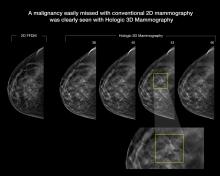

New research presented by Stephen Rose, M.D., chief medical officer of Solis Mammography and president of Rose Imaging Physicians Group, Houston, at the 2016 Radiological Society of North America (RSNA) annual meeting found recall rates, cancer detection and invasive cancer detection for women under age 50 were significantly improved with the addition of digital breast tomosynthesis (DBT) to mammography.1